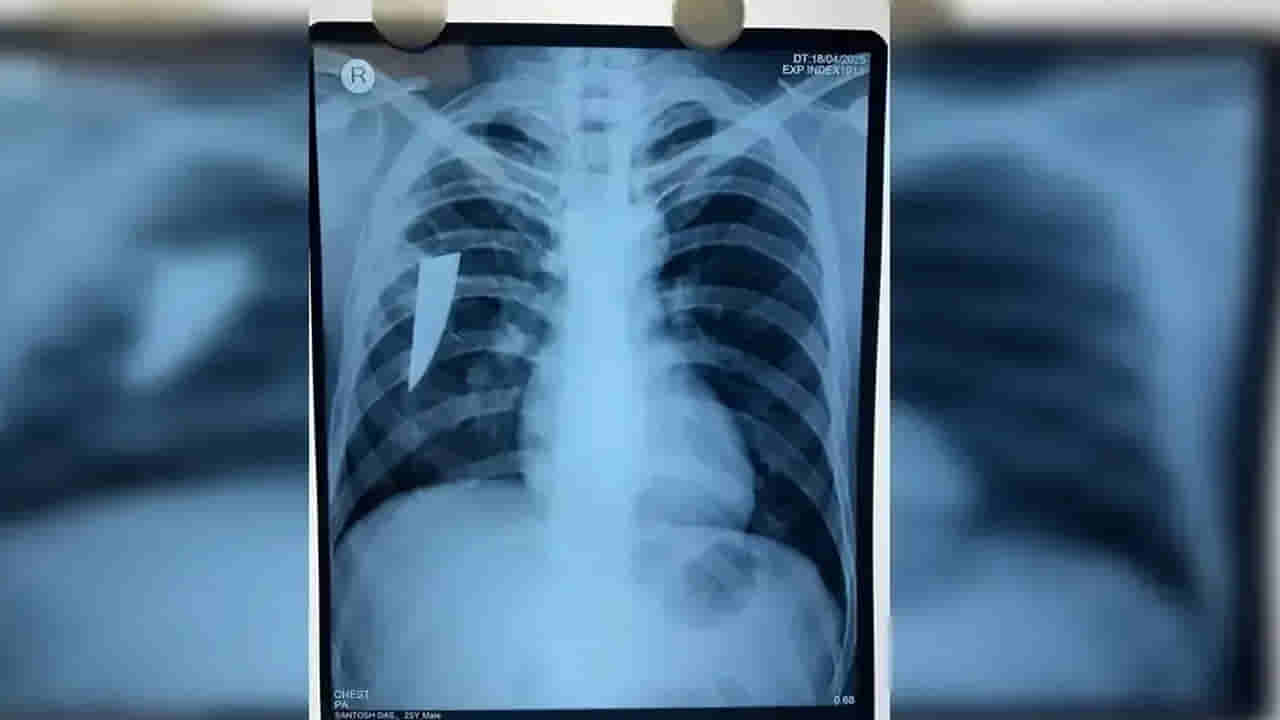

అది ఒడిశాలోని బెర్హంపూర్. అక్కడ గవర్నమెంట్ ఆధ్వర్యంలో నడిచే ఎంకేసీజీ మెడికల్ కాలేజ్ అండ్ హాస్పిటల్ ఉంది. 24 ఏళ్ల యువకుడికి దగ్గులో రక్తం పడుతూ ఉండటంతో.. ఏప్రిల్ 19న అతని కుటుంబ సభ్యులు అక్కడికి తీసుకుని వచ్చారు. దీంతో అతనికి పలు టెస్టులు చేశారు అక్కడి డాక్టర్లు. ఎక్స్ రే తీయగా అతని శరీరంలో ఏదో వస్తువు ఉన్నట్లు వెల్లడైంది. మరింత స్పష్టత కోసం.. CT స్కాన్, బ్రోంకోస్కోపీ చేయగా.. అతని కుడి ఊపిరితిత్తులో ఒక కత్తి ముక్క ఉన్నట్లు గుర్తించారు. వైద్యుల బృందం థొరాకోటమీ ఆపరేషన్ చేసి అతని ఊపిరితిత్తి నుంచి విజయవంతంగా ఎనిమిది సెంటీమీటర్ల పొడవున్న విరిగిన కత్తి ముక్కను తొలగించింది. ఆ కత్తి ముక్క వెడల్పు 2.5 సెం.మీ, మందం 3 మి.మీ ఉందని చెప్పారు. రోగి పరిస్థితి ప్రస్తుతం బాగానే ఉందని, ప్రస్తుతం ఆయన ఇంటెన్సివ్ కేర్ యూనిట్ (ఐసీయూ)లో పరిశీలనలో ఉన్నారని డాక్టర్లు తెలిపారు.